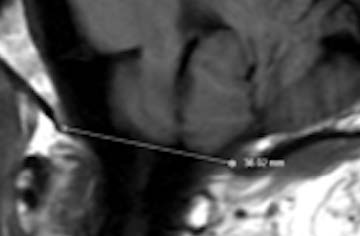

At Greenberg Regenerative Medicine in the greater Philadelphia area, we frequently treat patients with Ehlers-Danlos syndrome (EDS)—specifically the hypermobile form known as hEDS. This condition